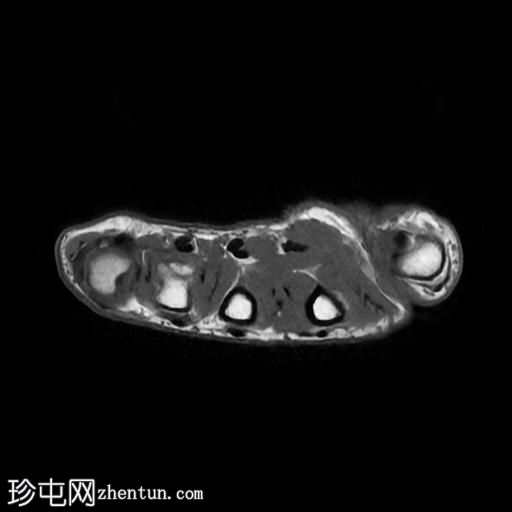

轴位

T1加权像

6.jpg